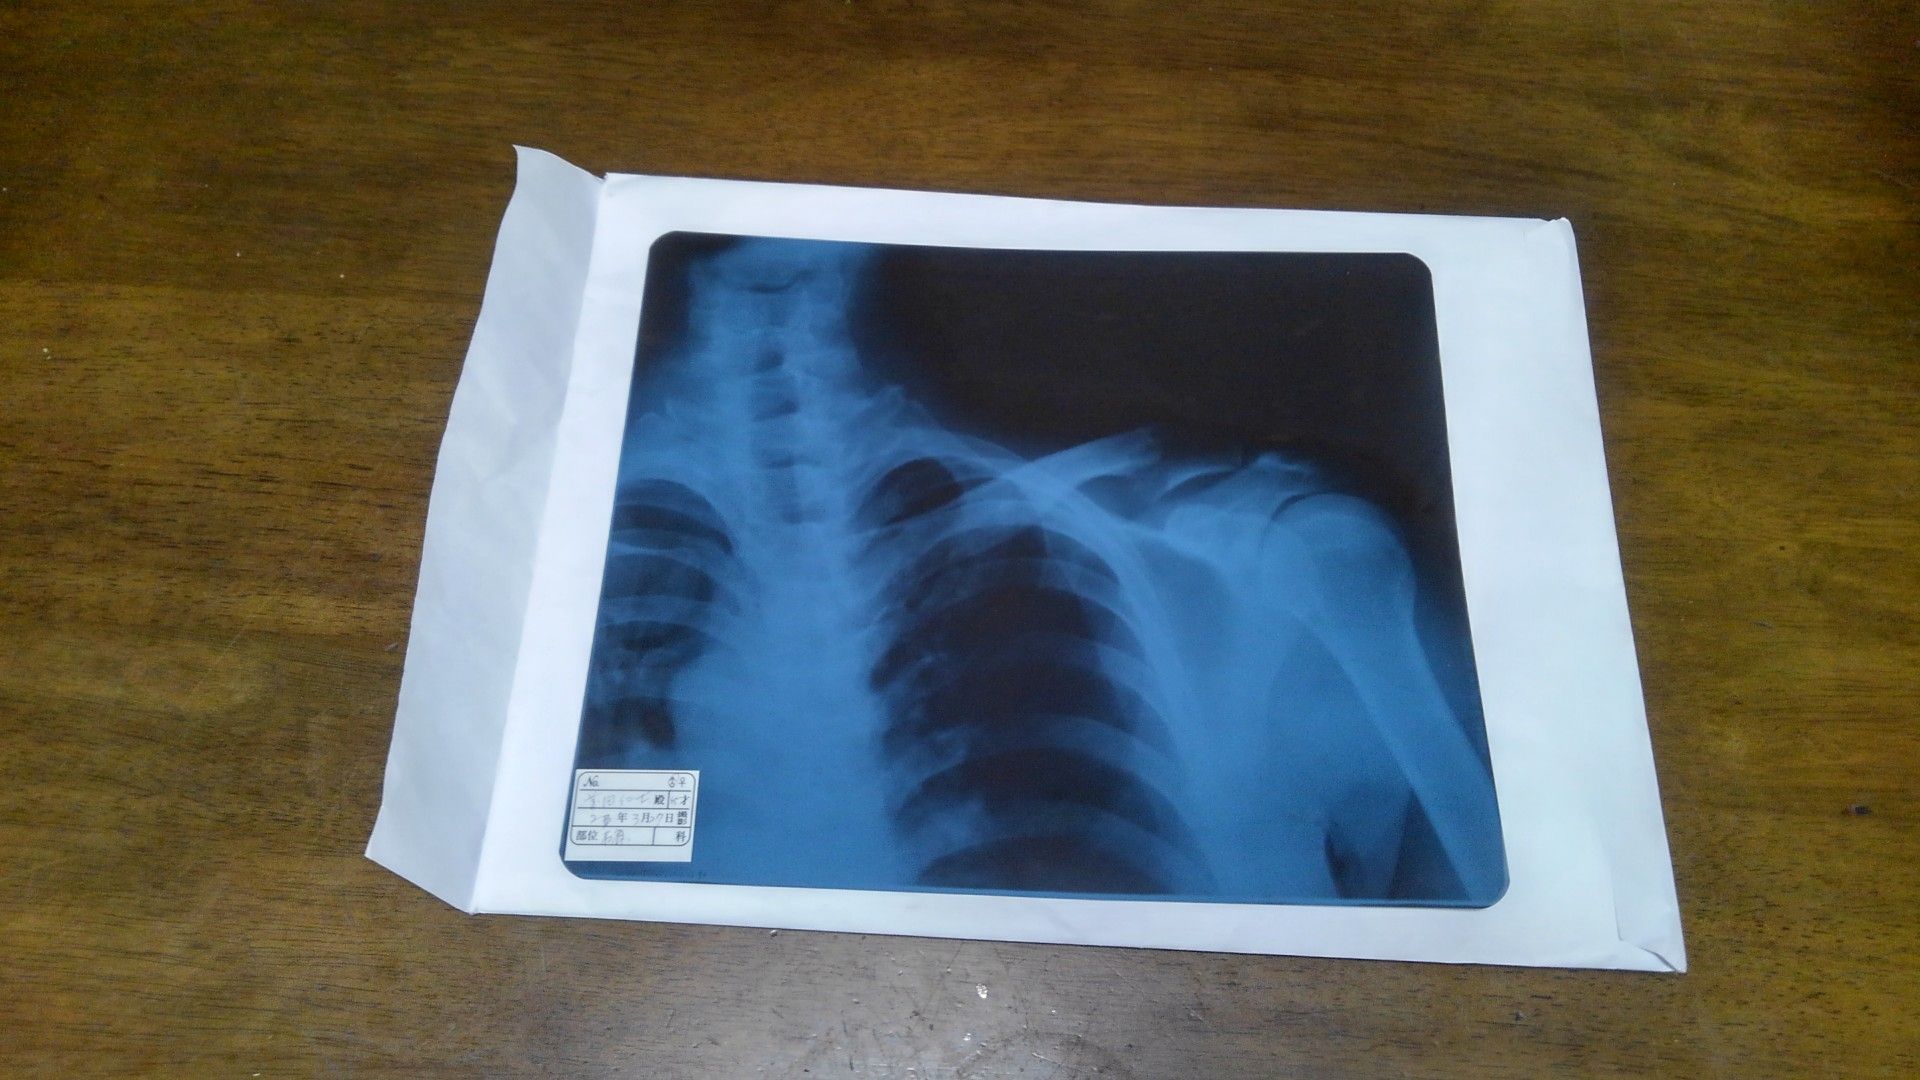

月曜日まで治療を待つのも気持ち悪いので、個人病院で親がお世話になっている整形外科に行きました。コロナの影響か、さほど待つことなく診察を受けました。レントゲンを撮って確認すると、先生曰く「折れた部分に一方の骨が挟まるようになっているので、装具で矯正しながら1週間様子を見て、まずければ手術」とのことでした。とりあえず、これで過ごすしかないが、今は患部が熱をもっていて微熱(37℃)状態です。鈍痛も続くのが、ちょっと辛いかな。